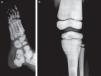

Presentation of the CaseA 4-year old male with a history of blindness in relation to congenital optic neuropathy of non-filiation aetiology and delayed growth. He presented at the emergency department after low intensity trauma in the right leg. An X-ray was taken which showed a fracture in the distal shaft of the tibia and fibula, together with a fracture callus in the proximal third of the fibula and general sclerosis of the visible bony structures which indicated sclerosing bone dysplasia (Fig. 1). The radiologic study was completed with a bone series, where a diffuse increase in bone density was highlighted with a “bone within bone” appearance and the enlargement of long bone metaphysis (Figs. 2–4). Radiologic findings determined the diagnosis of osteopetrosis.